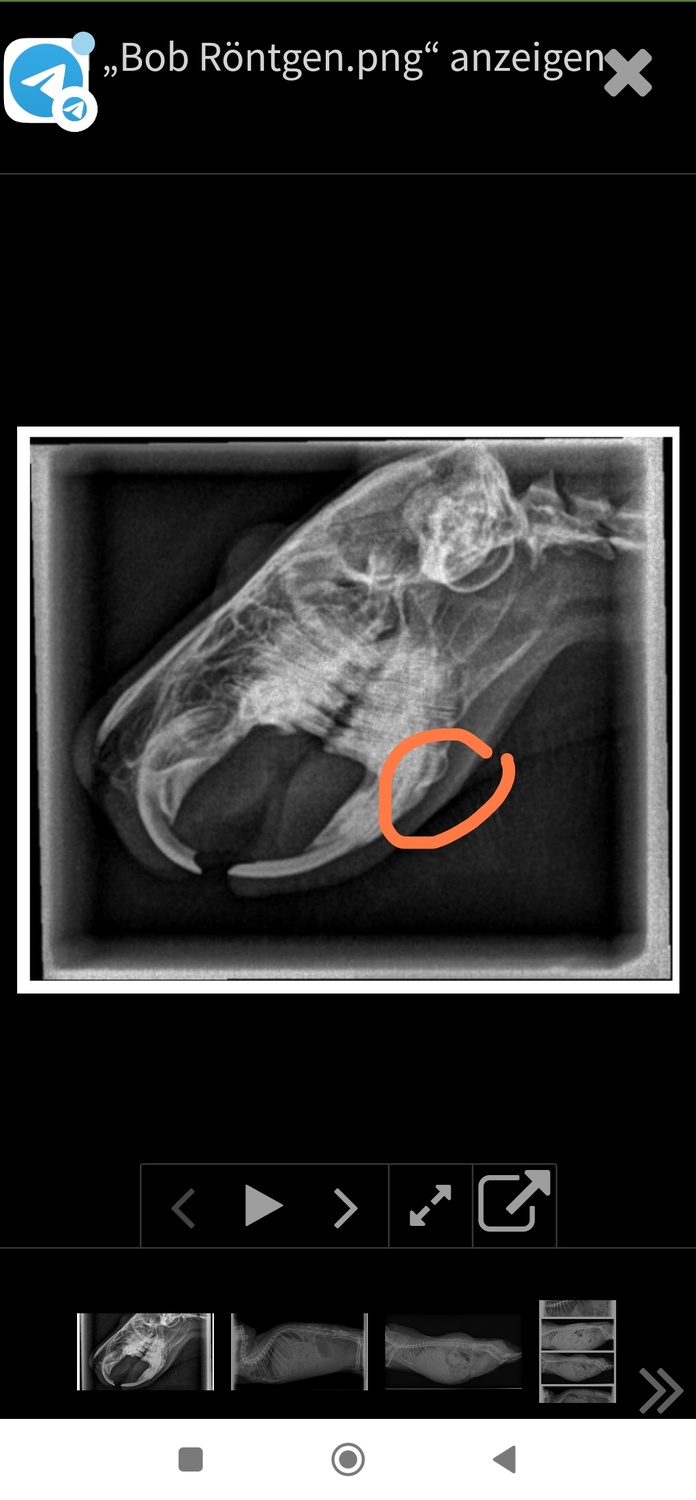

Zu dem Röntgenbild vom Kiefer, würde ich (als Laie) sagen, es besteht ein retrogrades Wachstum vom unteren Prämolaren (ob rechts oder links kann ich nicht sagen, da braucht es nochmal andere Aufnahmen). Dies kann, muss aber keine Probleme bereiten. Dazu hatte sich ja aber Silke schon geäußert.

Ob die Zähne allgemein zu lang sind oder nicht, kann man eigentlich nur mit Röntgen auf verschiedenen Ebenen mit entsprechenden Referenzlinien beurteilen.

Die Zähne sehen für mich deutlich zu lang aus. Das verursacht vermutlich auch den Aufbiss - und die retrograde Verlagerung. Leider kürzen viele Tierärzte anscheinend die Schneidezähne in solchen Fällen zu stark oder gar unnötig. Wenn die Backenzähne wieder "passen" können (nicht müssen) die Schneidezähne plötzlich auch wieder in der richtigen Stellung sein. Dagegen sind zu stark gekürzte Schneidezähne für das Tier frustrierend, weil es dadurch - selbst wenn es hinten stimmen sollte - 1-2 Wochen mindestens nicht abbeißen kann.